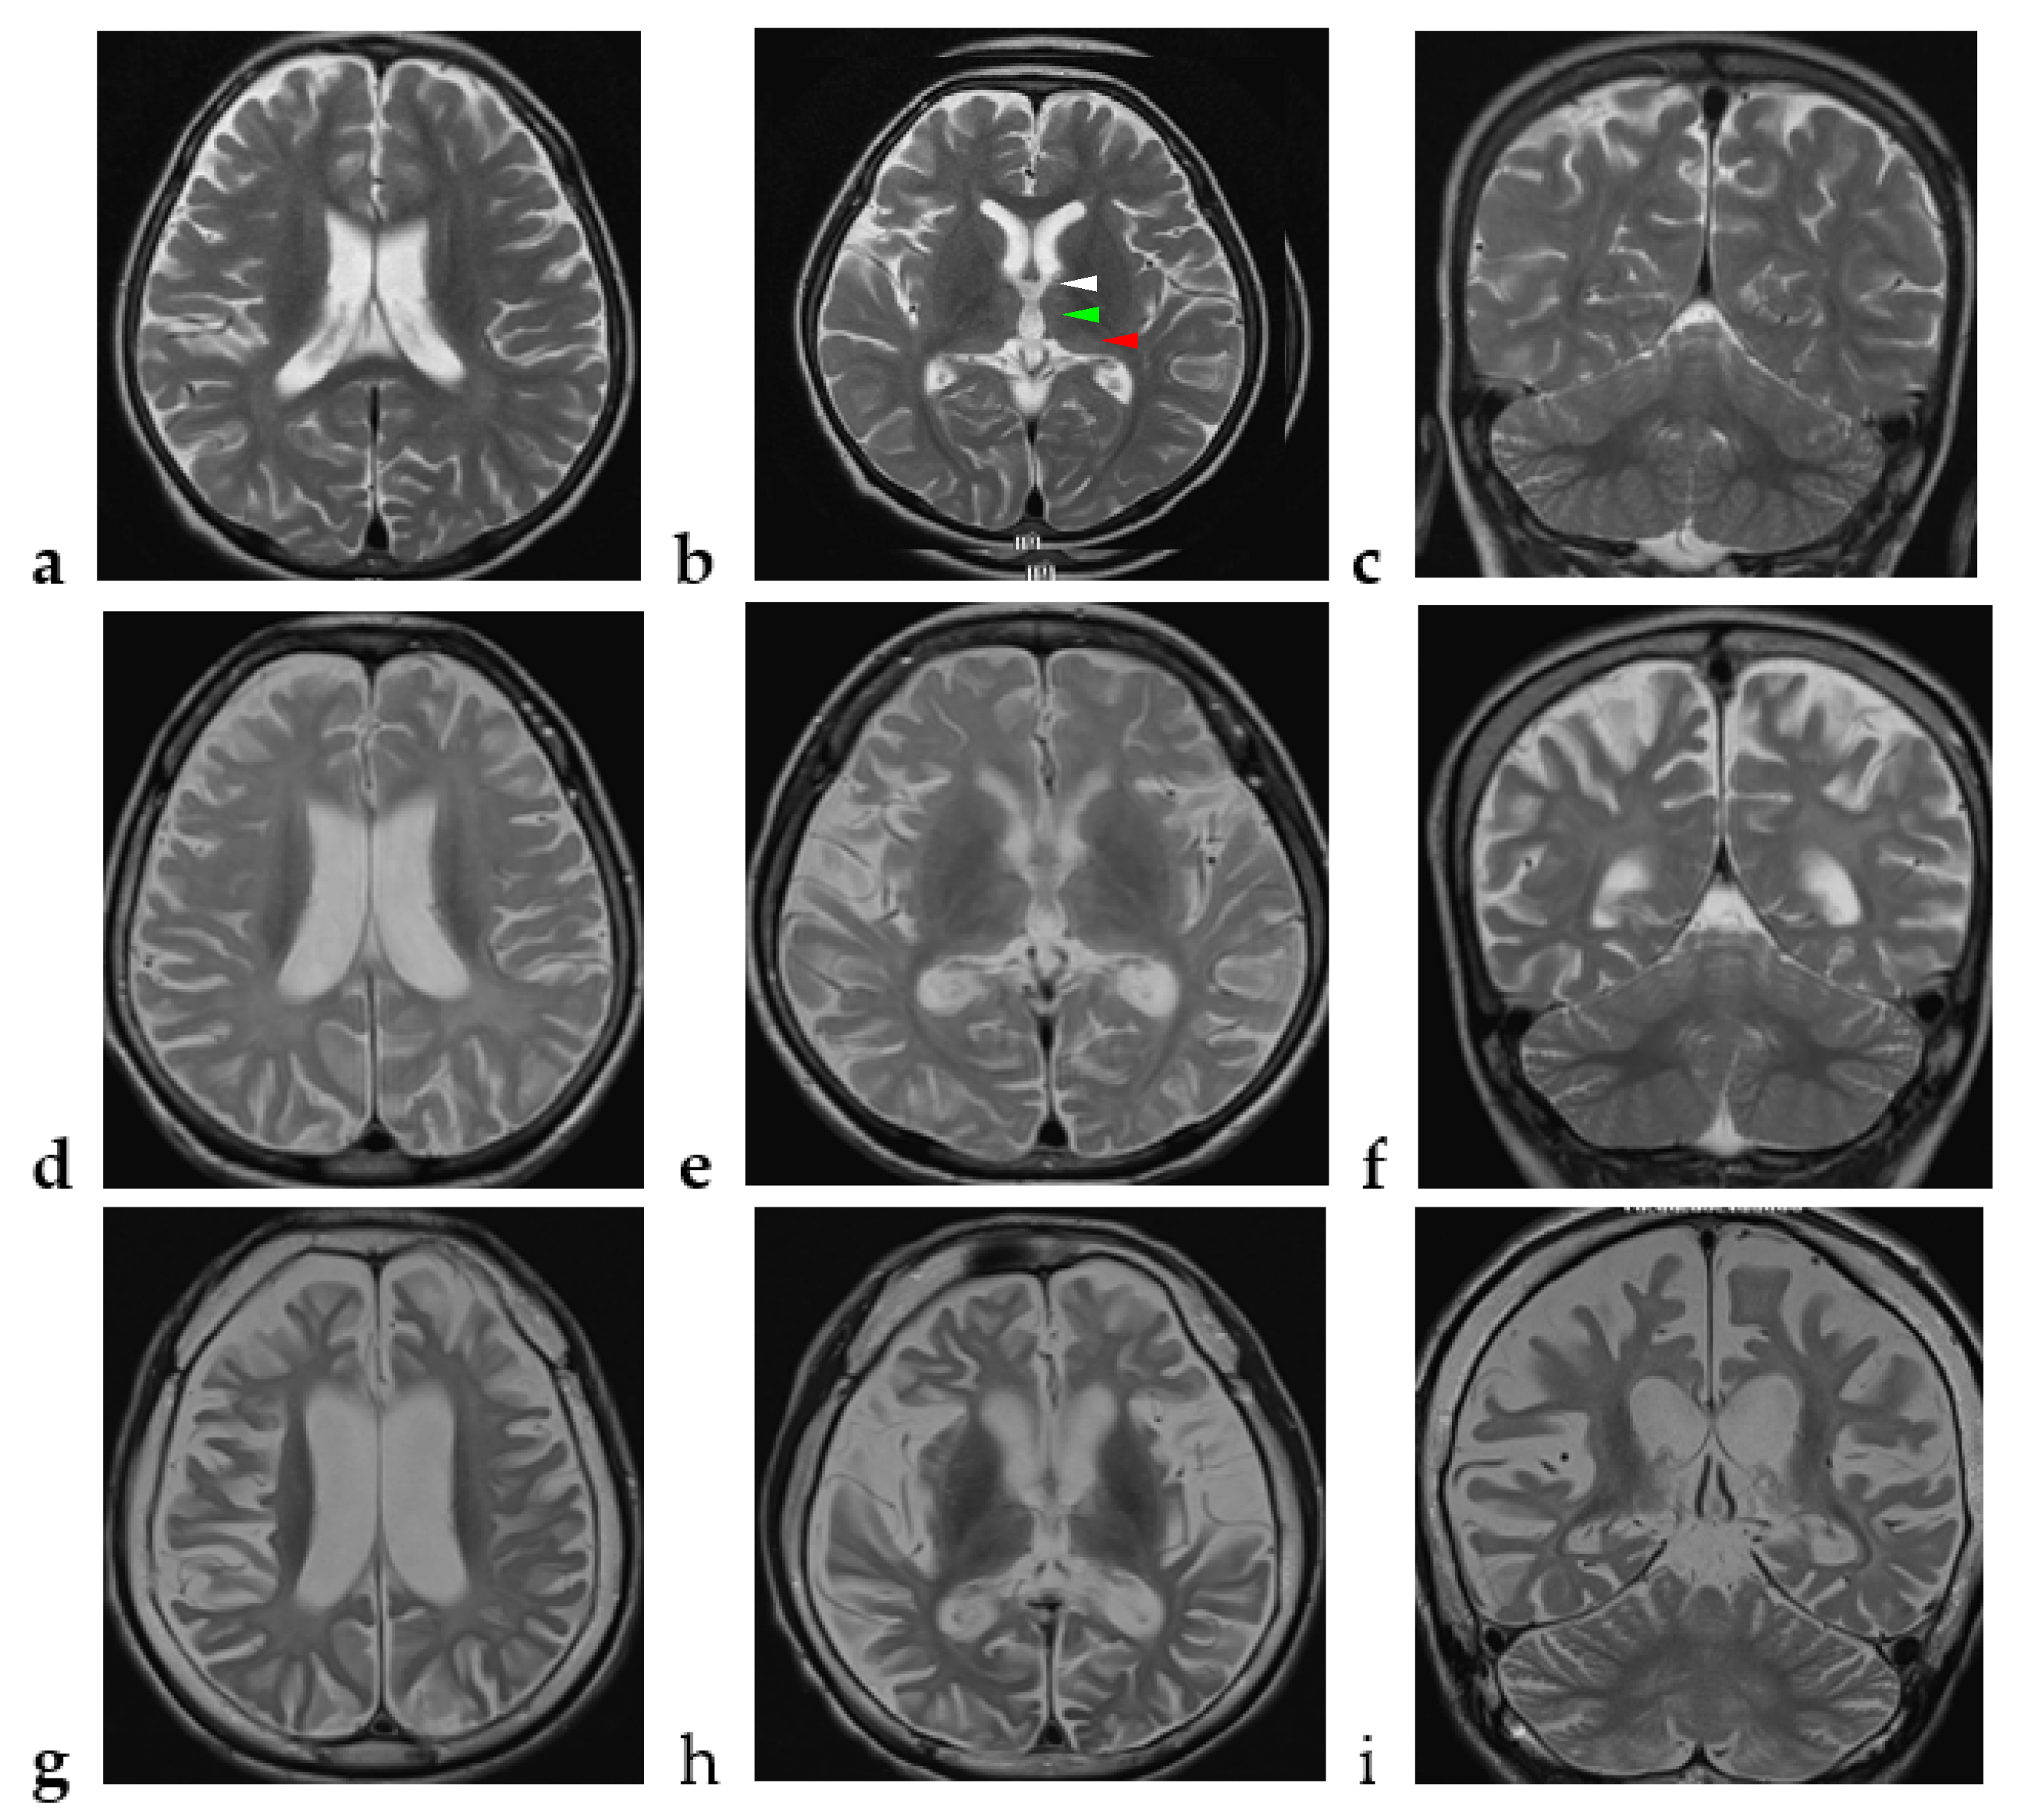

| Brain magnetic resonance imaging | |

| Supratentorial cerebral atrophy | 15 (100) |

| Cerebellar atrophy | 11 (73) |

| Diffuse white matter T2 hyperintensity | 12 (80) |

| Thalamus involvement | 2 (13) |